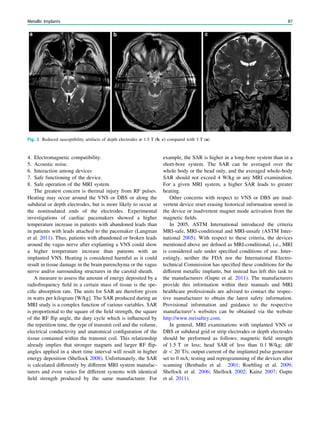

Fig. 1 Digital photogram of the brain surface before placement of a

results of electrical stimulations and ictal/ intraictal EEG activity. Blue

grid contacts represent the eloquent zone, which is the motor cortex in

this case. The black area represents the epileptogenic lesion, defined

as the radiographic lesion that causes the seizures. The yellow area is

the seizure onset zone, defined as the area from which the clinical

seizures are generated. The seizure onset zone is often, but not

necessarily, congruent with the epileptogenic zone, defined as the

cortex area indispensable for the generation of seizures

seizure onset zone which it is intended to be removed, and

this is defined as the brain area in which ictal EEG activity

starts. The epileptogenic lesion usually shows at least some

overlap with the seizure onset zone and is therefore a good

indicator for its localization (Fig. 1).